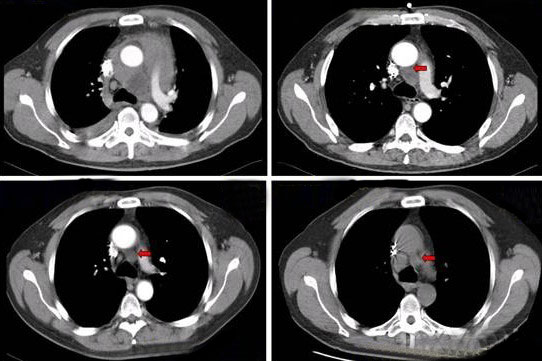

治疗前后CT影像对比图,标注肿瘤体积变化